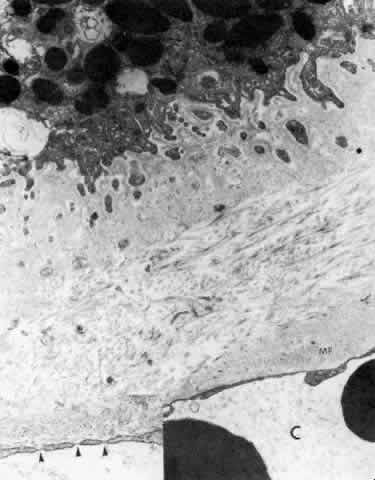

The cytoplasm of the PE cell is more electron-dense than that of the NPE cell, containing many free ribosomes, actin filaments, and predominantly cytokeratin-containing intermediate filaments (Fig. 25).26 The mitochondria are smaller and fewer in number than in the NPE, as is the RER, and the Golgi apparatus is present irregularly. There are large numbers of rounded and some elliptical melanin pigment granules of the 0.8 μm to 2 μm size characteristic of neuroepithelium, and three to four times larger than those of the stromal pigment cells. A decrease in pigment granules occurs in the PE over the crests of the ciliary processes from the fourth decade of life. Lipid droplets and complex lipopigment granules are seen within the cytoplasm during aging (see Fig. 25). The base of the PE cell is markedly infolded, lying on a basement membrane that with aging develops a thick, multilaminar pattern generally denser than that over the NPE cells but also containing vesicular, fibrillar, and granular inclusions (Fig. 26). The basement membrane of the PE is often very close to or almost continuous with that of the fenestrated capillaries in the pars plicata region (Fig. 27).

Fig. 25. Ciliary pigmented epithelial cells in mid pars plana of a young adult. The cytoplasm is electron-dense with many tonofilaments (T) (intermediate filaments). Lipid droplets (L) are present around dark lysosomal residual bodies. Desmosomes connect the cells (arrow). The basal surface and intercellular junctional areas are markedly infolded, and the basement membrane is moderately thick. Negative images of collagen fibers (COL) are seen below, in the dense stroma typical of this region (X 17,500)

Fig. 26. Inset. Greatly thickened basal lamina under pigmented epithelial cell in (pe) pars plicata of 80-year-old patient. c, capillary. Higher magnification of area in inset shows mixed multilaminar and solid basement membrane with fine filaments, vesicles, and granular clumps, after fixation with Alcian blue to preserve glycosaminoglycans. (X 41,600; inset, X 10,330)

Fig. 27. Ciliary body stroma under the processes, anterior pars plicata. Even at age 19, the basement membrane is thick. Collagen and other fine filaments fill the narrow space between epithelium and fenestrated capillary wall (C). Inset. Arrowheads indicate fenestrae in wall. Clumps of tubular microfibrils (MF) of the elastic system are closely associated with the capillary wall. (X 17,300; inset, X 43,000)